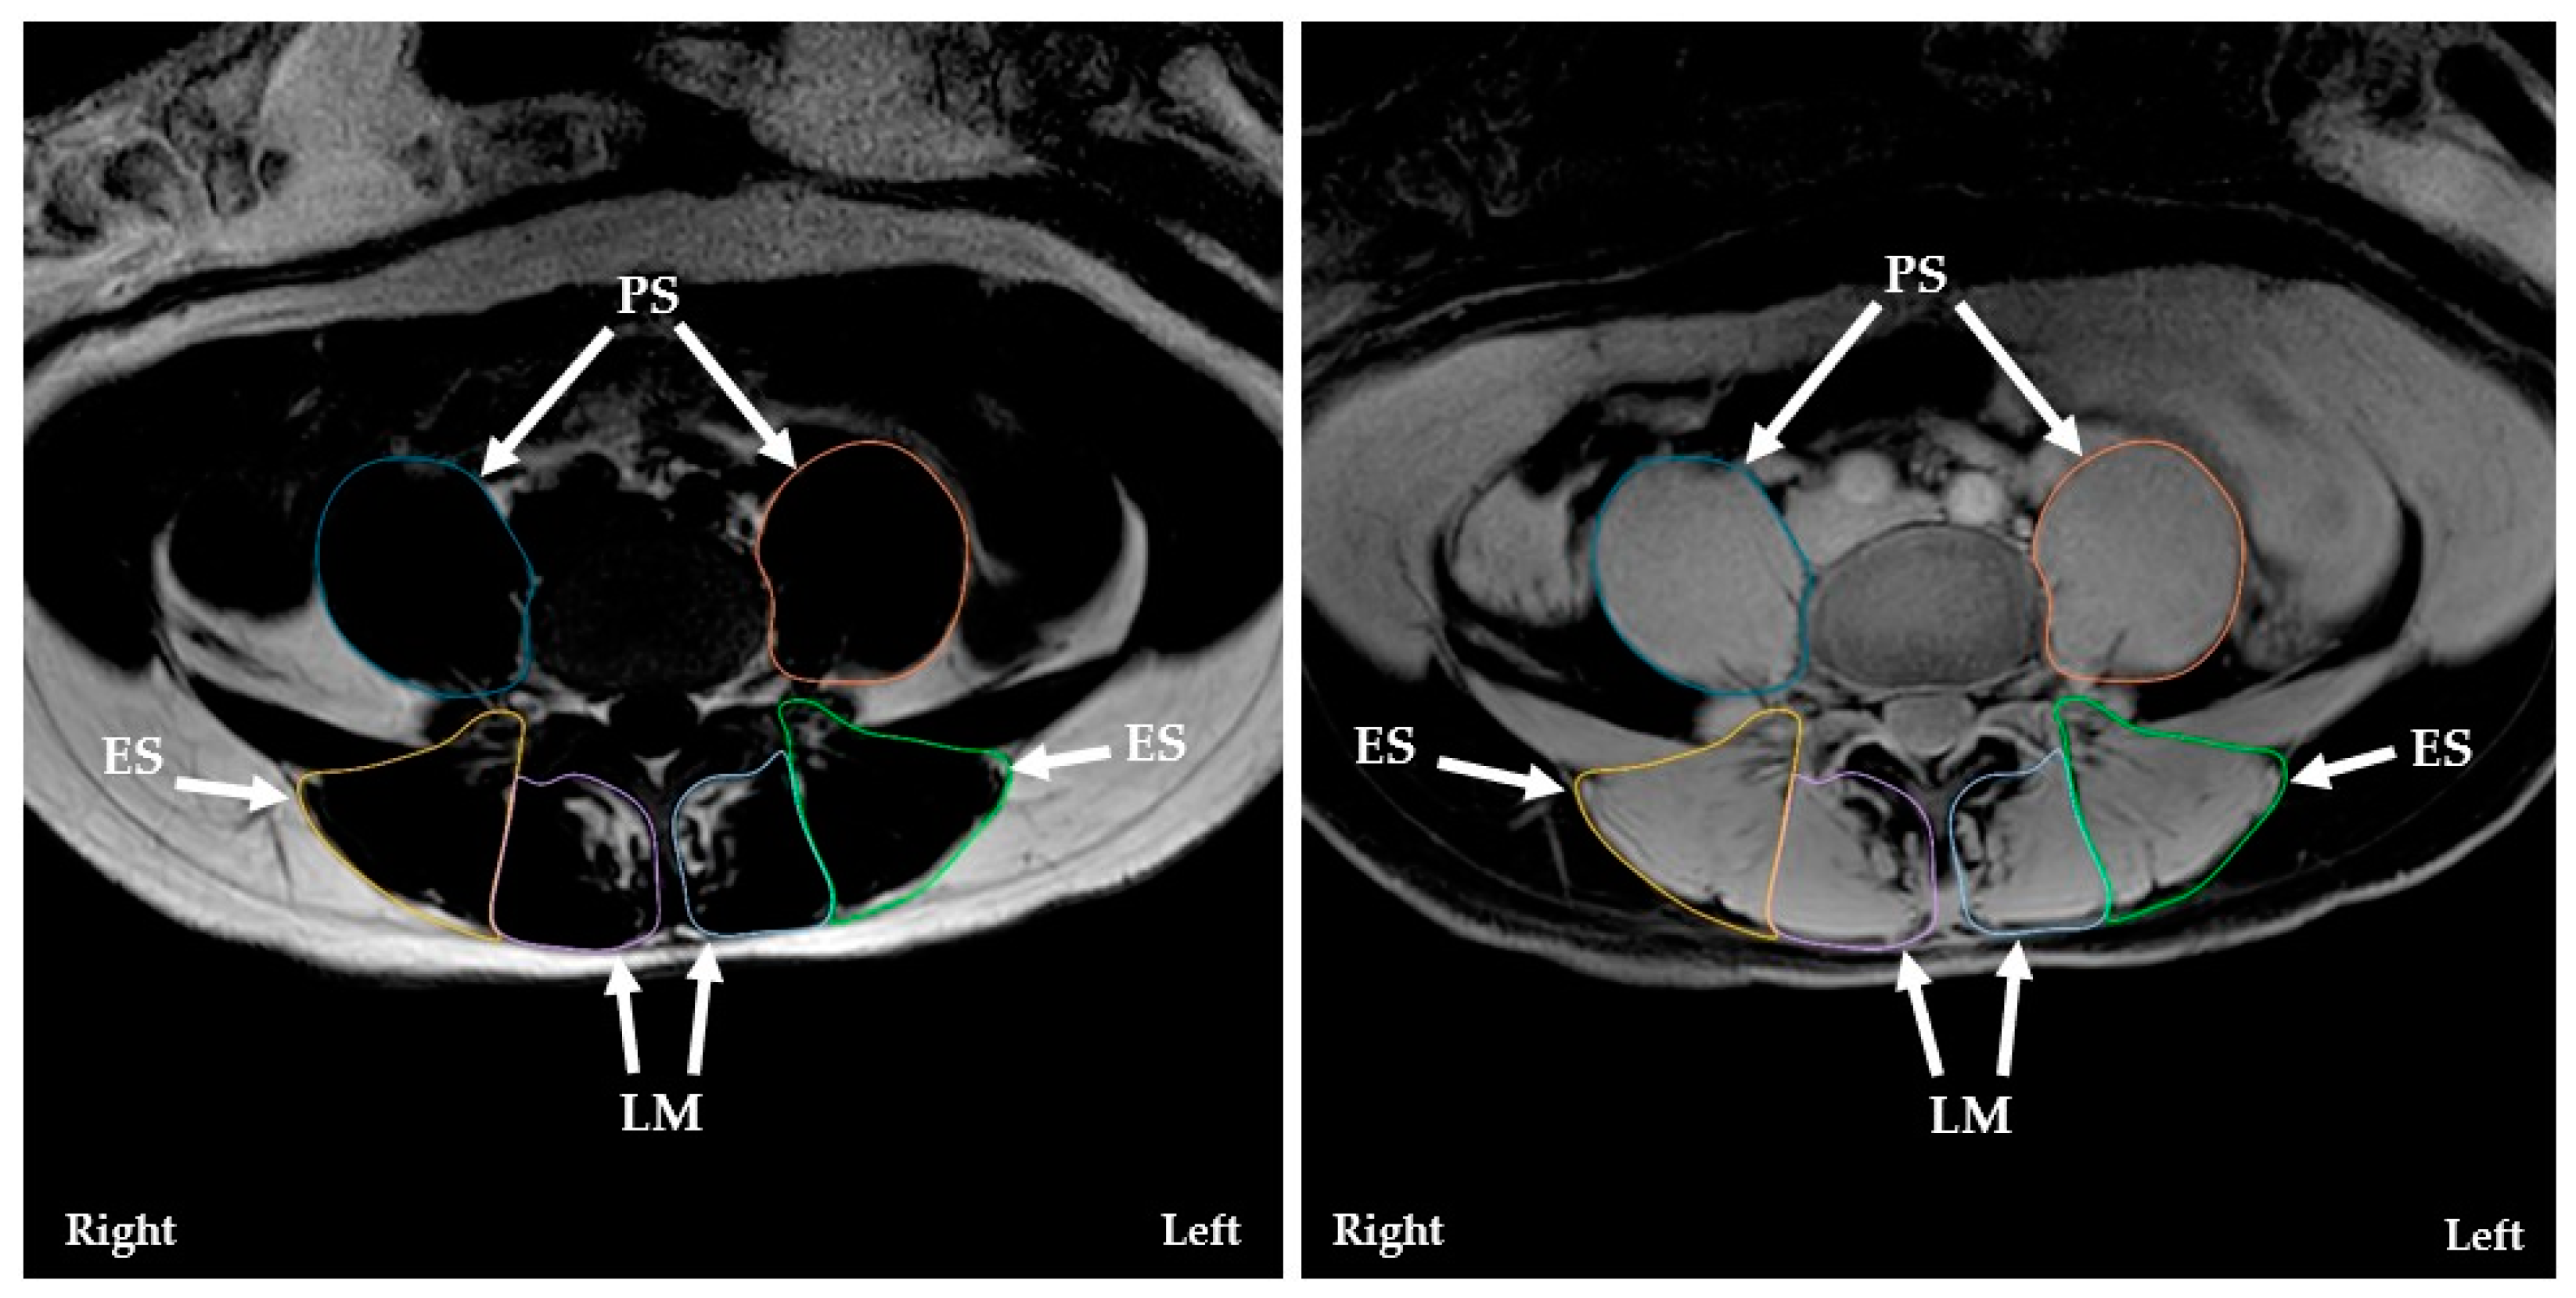

2.5. Paraspinal Muscle Measurements